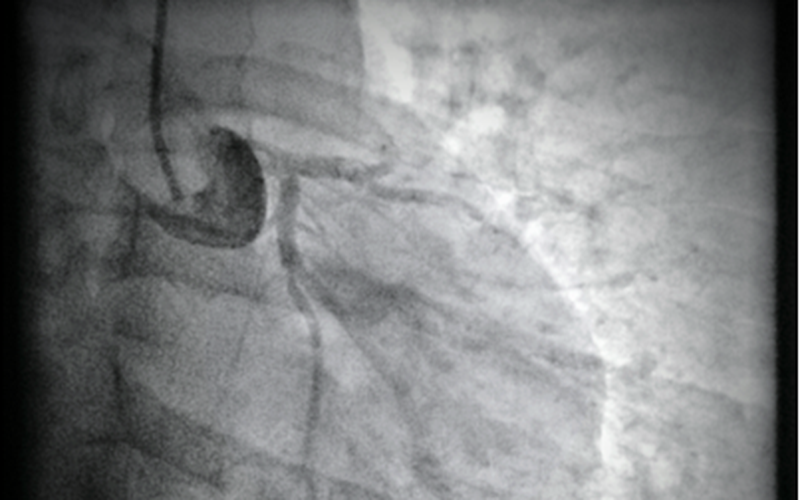

Kết quả chụp động mạch vành cho thấy: Tắc hoàn toàn nhánh liên thất trước của động mạch vành trái. Bệnh nhân được can thiệp đặt 1 stent vào vị trí động mạch bị tắc.